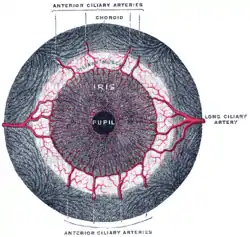

Interior of anterior half of bulb of eye. (Choroid labeled at right, second from the bottom.) | |

Iris, front view The terminal portion of the optic nerve and its entrance into the eyeball, in horizontal section